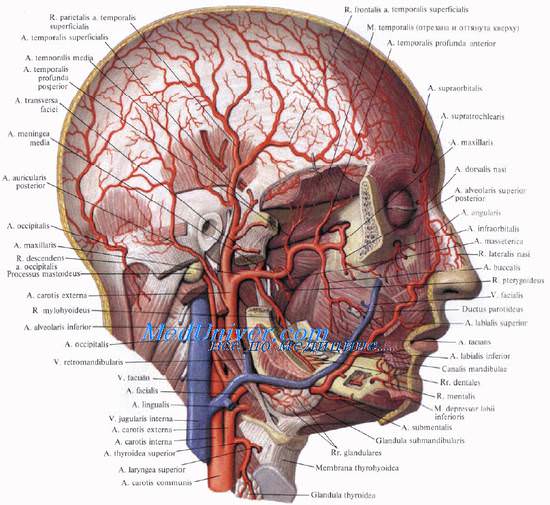

Кровоснабжение, иннервация полости носа и лимфоотток

Кровоснабжение, иннервация полости носа и лимфоотток Главной артерией, питающей стенки носовой полости, является a. sphenopalatine (из a. maxillaris). В передней части полости разветвляются аа. ethmoidales anterior et posterior (от a. ophthalmica). Вены наружного носа вливаются в v. facialis и v. ophthalmica.

Кровоснабжение наружного носа осуществляется a. dorsalis nasi (конечная ветвь a. ophthalmica) и ветвями лицевой артерии. Вены связаны с лицевыми венами и с истоками глазных вен.

Кровоснабжение околоносовых пазух происходит из ветвей внутренней и наружной сонных артерий, главным образом через глазную и верхнечелюстные артерии. Вены гайморовой пазухи анастомозируют с венами лица и крыловидного сплетения, а вены лобной пазухи — с венами твердой мозговой оболочки, с продольным синусом и пещеристым синусом. По этим путям иногда проникает инфекция в глазницу или полость черепа.